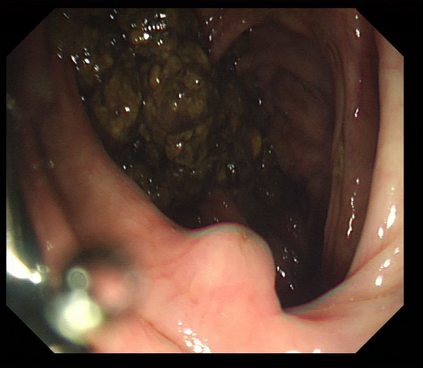

Polyps are early cancer indicators, so assessing occurrences of polyps and their removal is critical. They are observed through a colonoscopy screening procedure that generates a stream of video frames. Segmenting polyps in their natural video screening procedure has several challenges, such as the co-existence of imaging artefacts, motion blur, and floating debris. Most existing polyp segmentation algorithms are developed on curated still image datasets that do not represent real-world colonoscopy. Their performance often degrades on video data. We propose a video polyp segmentation method that performs self-supervised learning as an auxiliary task and a spatial-temporal self-attention mechanism for improved representation learning. Our end-to-end configuration and joint optimisation of losses enable the network to learn more discriminative contextual features in videos. Our experimental results demonstrate an improvement with respect to several state-of-the-art (SOTA) methods. Our ablation study also confirms that the choice of the proposed joint end-to-end training improves network accuracy by over 3% and nearly 10% on both the Dice similarity coefficient and intersection-over-union compared to the recently proposed method PNS+ and Polyp-PVT, respectively. Results on previously unseen video data indicate that the proposed method generalises.